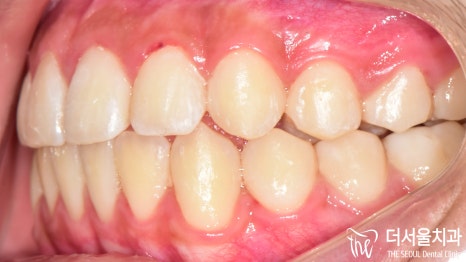

『결과』

전과는 달리 벌어졌던 이 사이도

긴밀하게 붙어 있는 것이 확인되었으며

툭 튀어나와 있던 돌출입도 개선이 되었습니다.

인비절라인 을 사용한 덕인지

이갈이 가 심한데도 불구하고

구강 내 상처나 치아 마모 등이 나타나지 않았네요.

아예 증상이 사라진 것은 아니지만

전보다 확실히 편해졌다던 말씀을 하셨는데요.